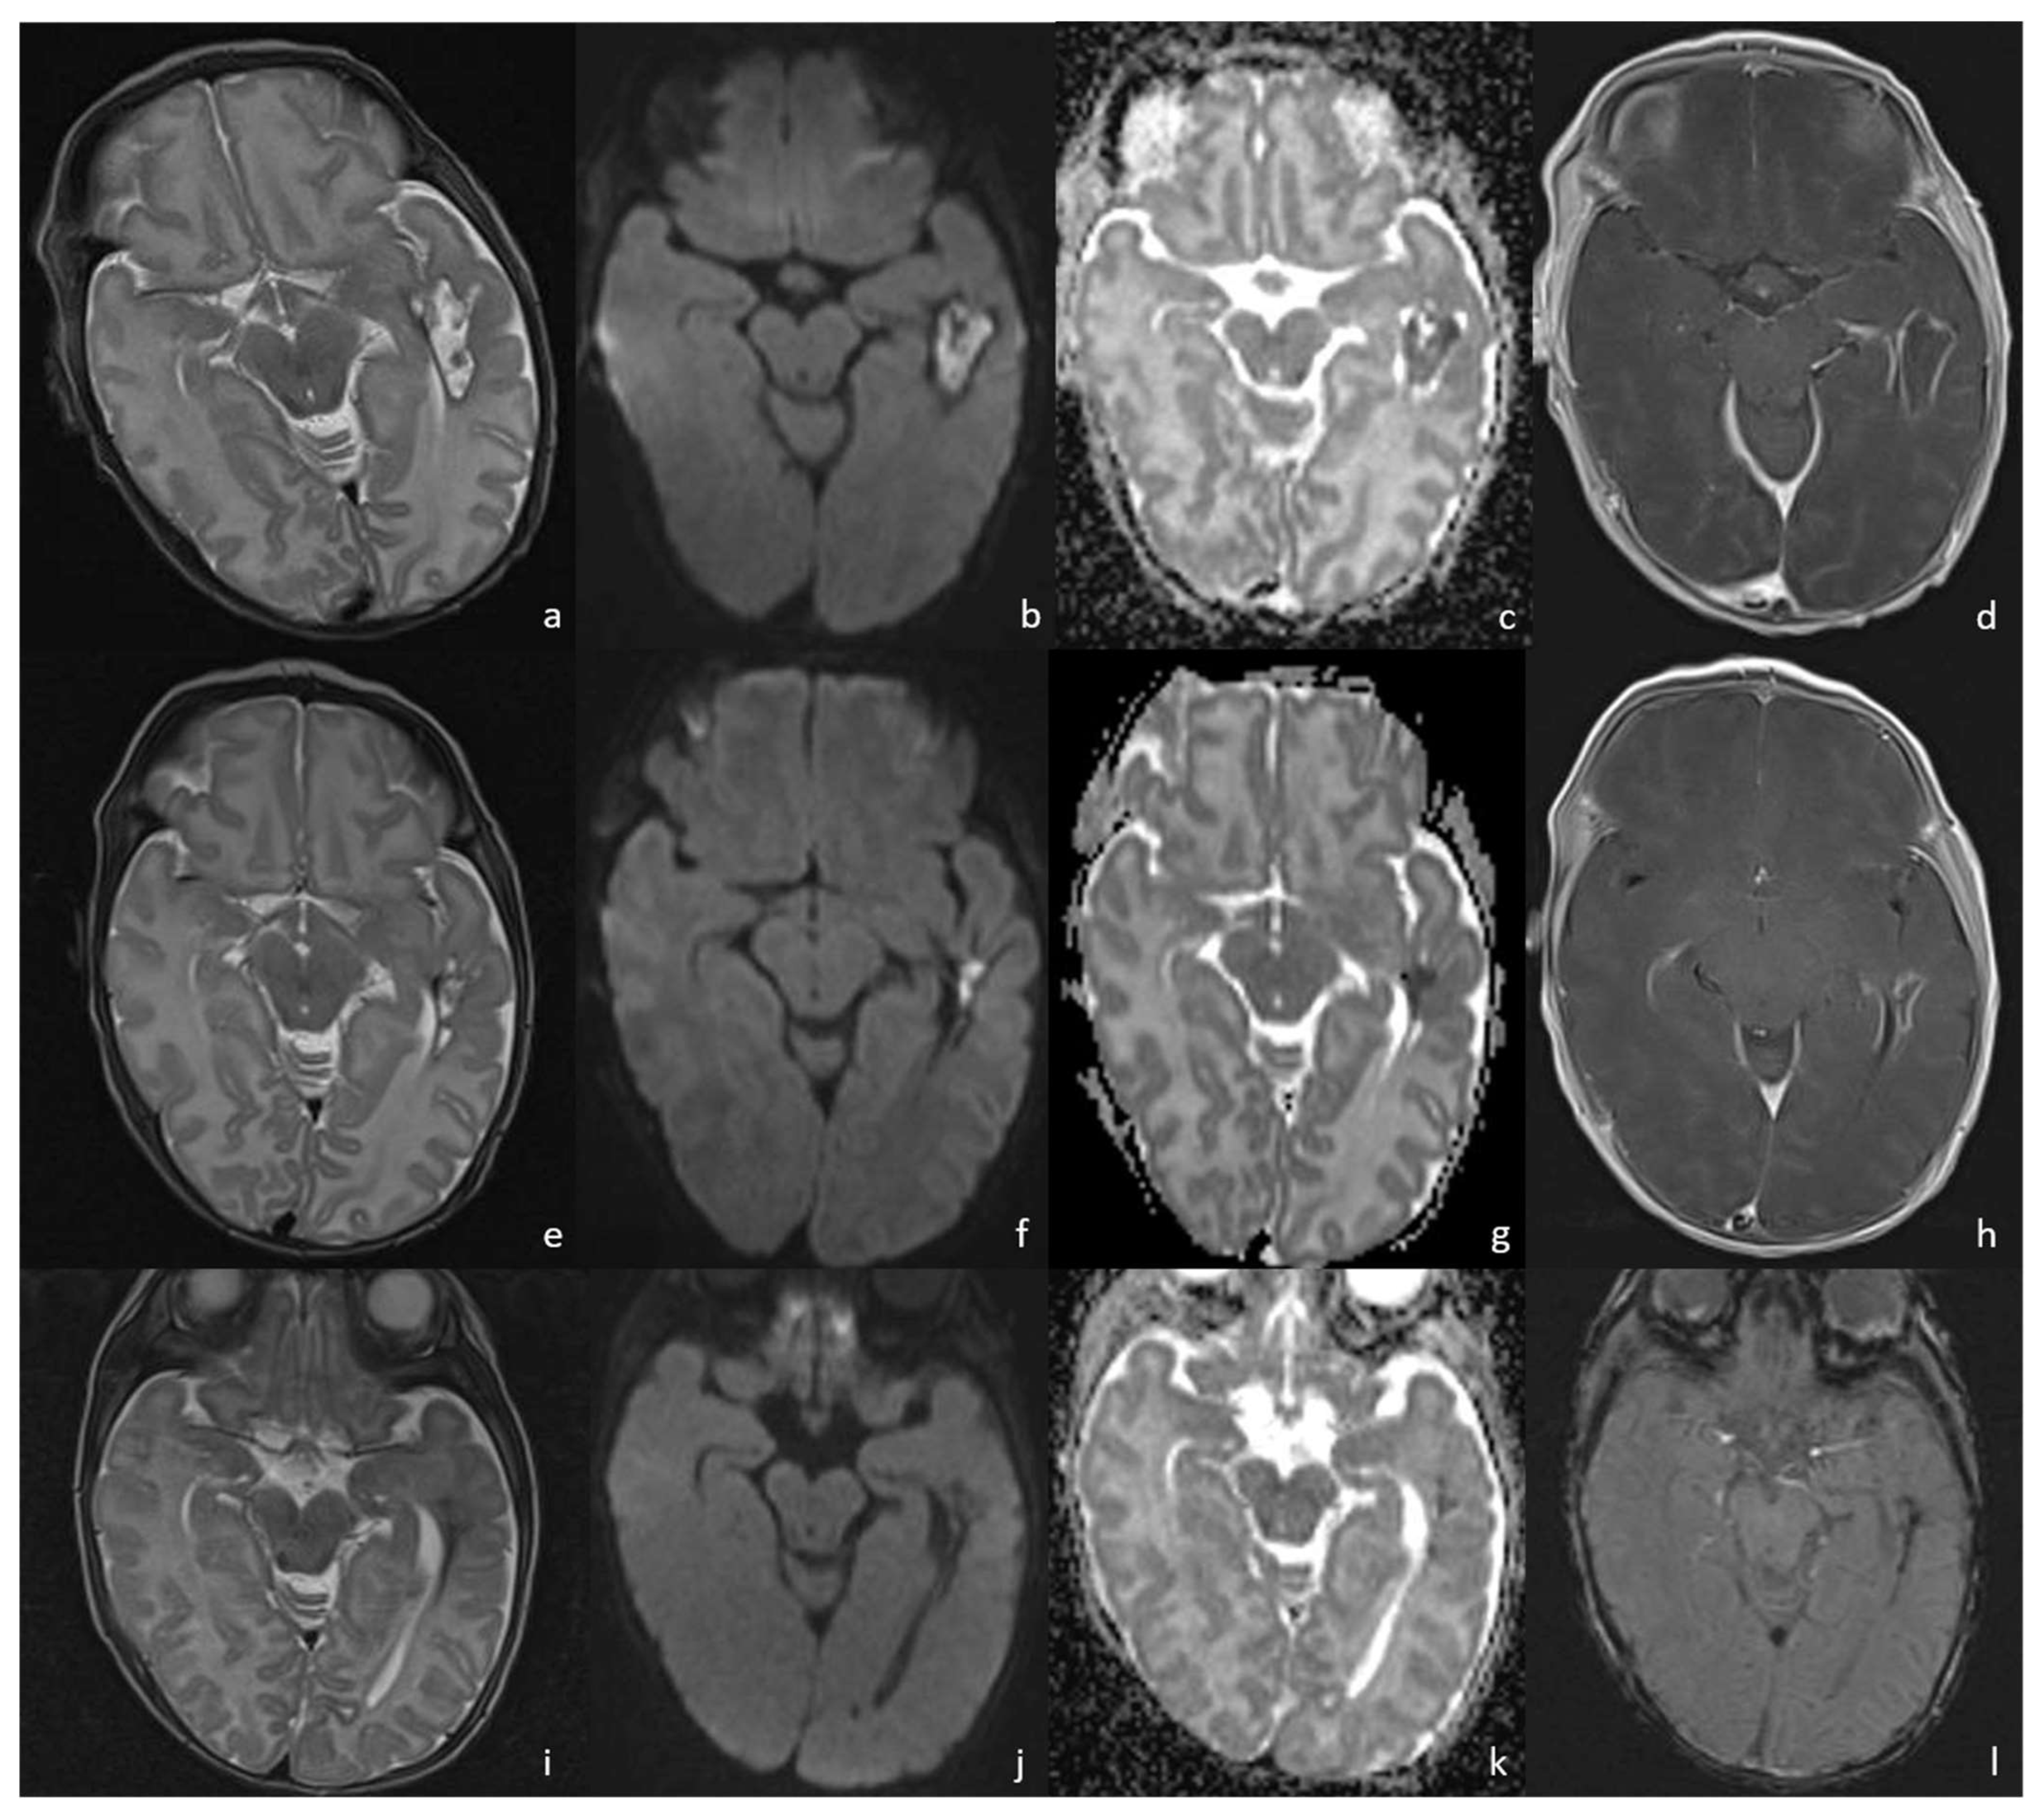

Figure 8.

A patient affected by Bacillus Cereus meningoencephalitis. MRIs were acquired at 30 days, 43 days, and 63 days from birth and show the brain abscess evolution during the patient’s follow-up. At 30 days from birth (a–d), the parenchymal abscess in the left temporal lobe presents a necrotic core, appearing inhomogeneously hyperintense on T2WI (a) with diffusion restriction on DWI/ADC (b,c), and a thick capsule, appearing hypointense on T2WI with intense enhancement on post-contrast T1WI (d). At 43 days from birth, the parenchymal abscess shows a dimensional decrease and similar radiological features on T2WI (e), DWI (f), ADC (g), and post-contrast T1WI (h). At 63 days we can appreciate a hemosiderin scar appearing hypointense on T2WI (i) and SWI (l) with no diffusion restriction on DWI/ADC (j,k).